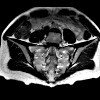

MRI of the sacroiliac joints.

МРТ крестцово-подвздошных суставов. Неинвазивный метод диагностики, позволяющий визуализировать крестцово-подвздошные суставы путем сканирования радиоволнами в условиях сильного магнитного излучения. Он предоставляет серию изображений с последующей программной обработкой и созданием объемной модели исследуемых анатомических структур. Это наиболее информативный способ визуализации хряща, связок и мышц этой области. Он используется в качестве дополнительного метода исследования при недостаточной информативности рентгеновских и компьютерных томографов при диагностике воспалительных, дегенеративных, травматических и онкологических поражений. Он имеет высокую диагностическую ценность при раннем выявлении сакроилеита у пациентов с болезнью Бехтерева, а также при распознавании некоторых видов серонегативного артрита.